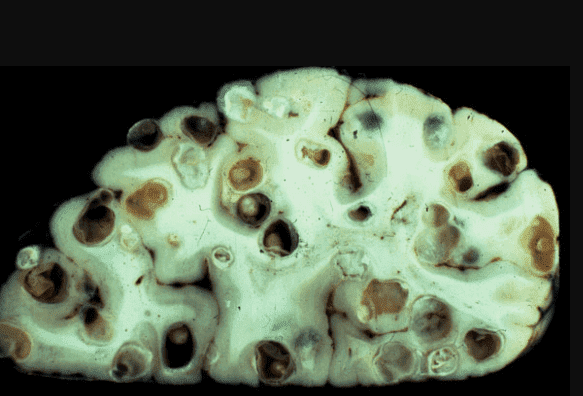

Мозок, уражений паразитами

Ще одна недавня історія. Пацієнтка померла від раку кишківника, спричиненого паразитами. Паразити отруюють здорові клітини своїми токсинами, через що вони змушені перероджуватися, змінювати свою структуру. І перероджуються вони саме в ракові клітини, які агресивніші й здатні протистояти паразитам. Але для людини ці клітини згубні. Пухлина швидко розвивається і пускає метастази. Людина гине протягом лічених місяців.

На фото нижче можете побачити знімок кишечника. Пацієнтка померла від раку кишківника, спричиненого паразитами. Паразити отруюють здорові клітини своїми токсинами, через що вони змушені перероджуватися, змінювати свою структуру. І перероджуються вони саме в ракові клітини, які агресивніші й здатні протистояти паразитам. Але для людини ці клітини згубні. Пухлина швидко розвивається і метастазує. Людина гине протягом лічених місяців.

"Ходи" паразитів у просвіті кишечника